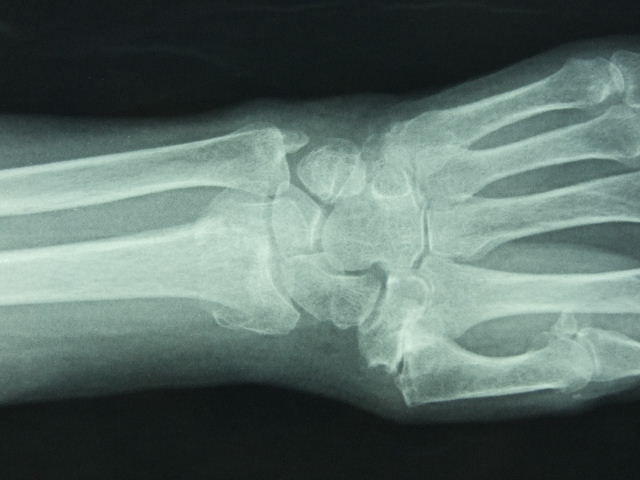

Carpo normal

ACT Alteraciones degenerativas en muñeca.